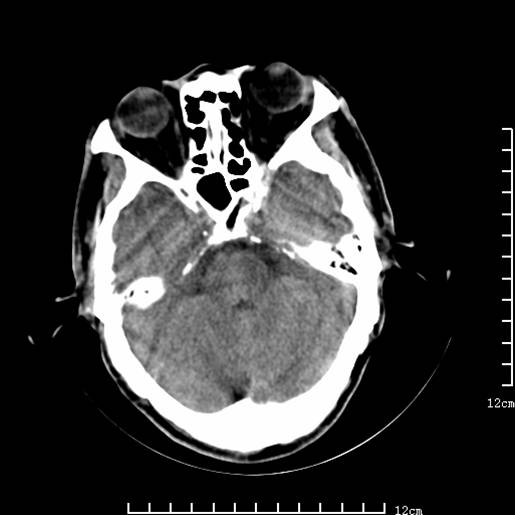

以下图像分别是3月25日凌晨及下午图像、3月27日、4月16日的ct图像。

3月25日凌晨